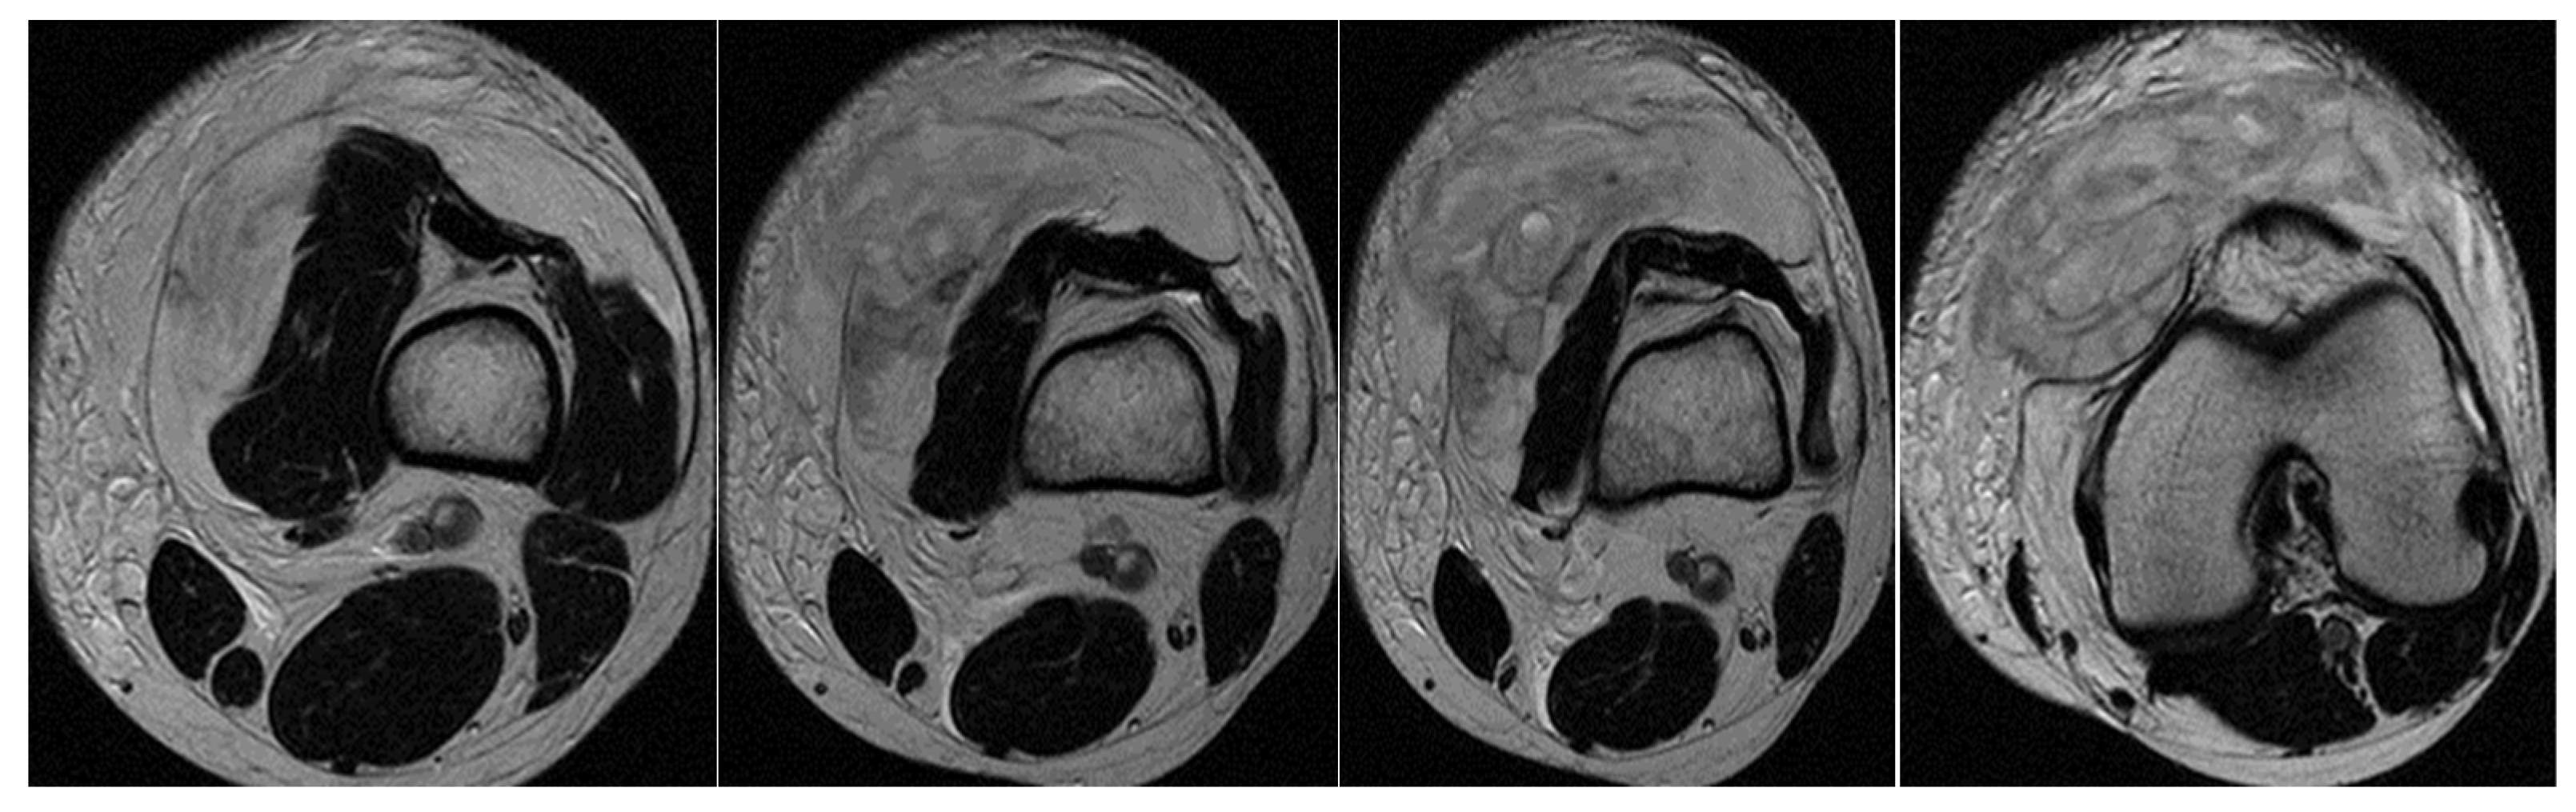

3.1. Case 1: Vastus Lateralis Tear with Prepatellar Hematoma

Right back, 22 years old, national-team player from a rural area, professional first-league athlete, 198 cm, 110 kg. In the initial case, the right back sustained injuries to the knee and the distal portion of the left thigh during a training session, attributed to a lateral concussion and the “opening” of the internal compartment. The clinical examination revealed pain, swelling, edema, a bubble knee, relative functional impairment, and restricted active and passive movement of the left knee. A sprain of the left knee was suspected, with potential damage to the meniscus, cruciate ligaments, and collateral ligaments. Although the MRI did not indicate any damage to the intra-articular structures, it did reveal a substantial prepatellar extraarticular hematoma, resulting from a muscle tear in the vastus lateralis muscle, along with significant edema of the soft tissue. The extraarticular edema is evident in the non-homogeneous Ts and STIR hyperintense, accompanied by T1 hypo- and hyperintense. Post-traumatic edema of the adjacent soft tissue is depicted in STIR as an altered diffused hyperintense (Figure 1, Figure 2 and Figure 3).

Figure 2.

Knee MRI: axial T2 acquisition.

Figure 3.

Knee MRI: coronal stir acquisition.

Treatment consisted of myorelaxant medication, cryotherapy, and local applications of heparin gel in the first stage, followed by physical and kinetotherapy to prevent the hematoma from becoming chronic and infected and regain knee mobility and return to full training after 6 weeks.